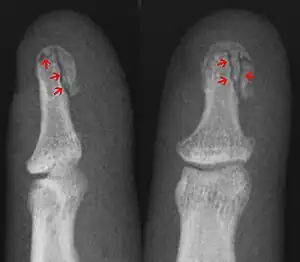

Internal and external views of an arm with a compound fracture, both before and after surgery

In the fingertip. More images